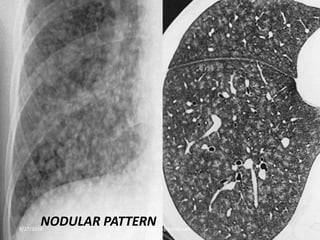

Nodular Pattern :

Three categories: according to their distribution

A. Random

B. Centrilobular

C. Perilymphatic

Random distribution:

-Random refers to no preference for a specific location

in the secondary lobule.

-Nodules are randomly distributed relative to

structures of the lung and secondary lobule.

-Nodules can usually be seen to involve the pleural

surfaces and fissures, but lack the subpleural

predominance.8/27/2019 zannatulrayhan@gmail.com

Centrilobular distribution:

-nodules are limited to the centrilobular region.

-centrilobular nodules spare the pleural surfaces.

-most peripheral nodules are centered 5-10 mm from

fissures or the pleural surface.

Perilymphatic distribution:

- nodules are seen in relation to pleural surfaces,

interlobular septa and the peribronchovascular

interstitium.

-Nodules are almost always visible in a subpleural

location, particularly in relation to the fissures.

NODULAR PATTERN8/27/2019 zannatulrayhan@gmail.com